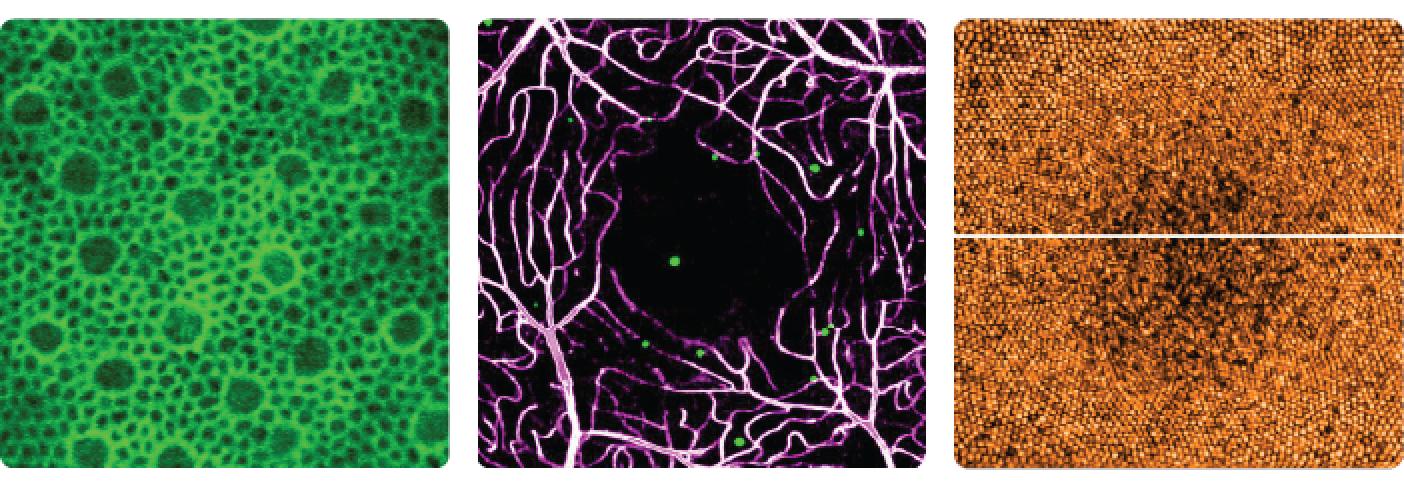

Dr. Johnny Tam and his team are using a powerful imaging technique called adaptive optics to take ultra-sharp pictures of the living retina. These images are precise enough to see individual cells, showing details that were once invisible to researchers and providers.

These detailed images of human retina cells were captured using NEI's custom-built adaptive optics ophthalmoscopes. View more in our image gallery.